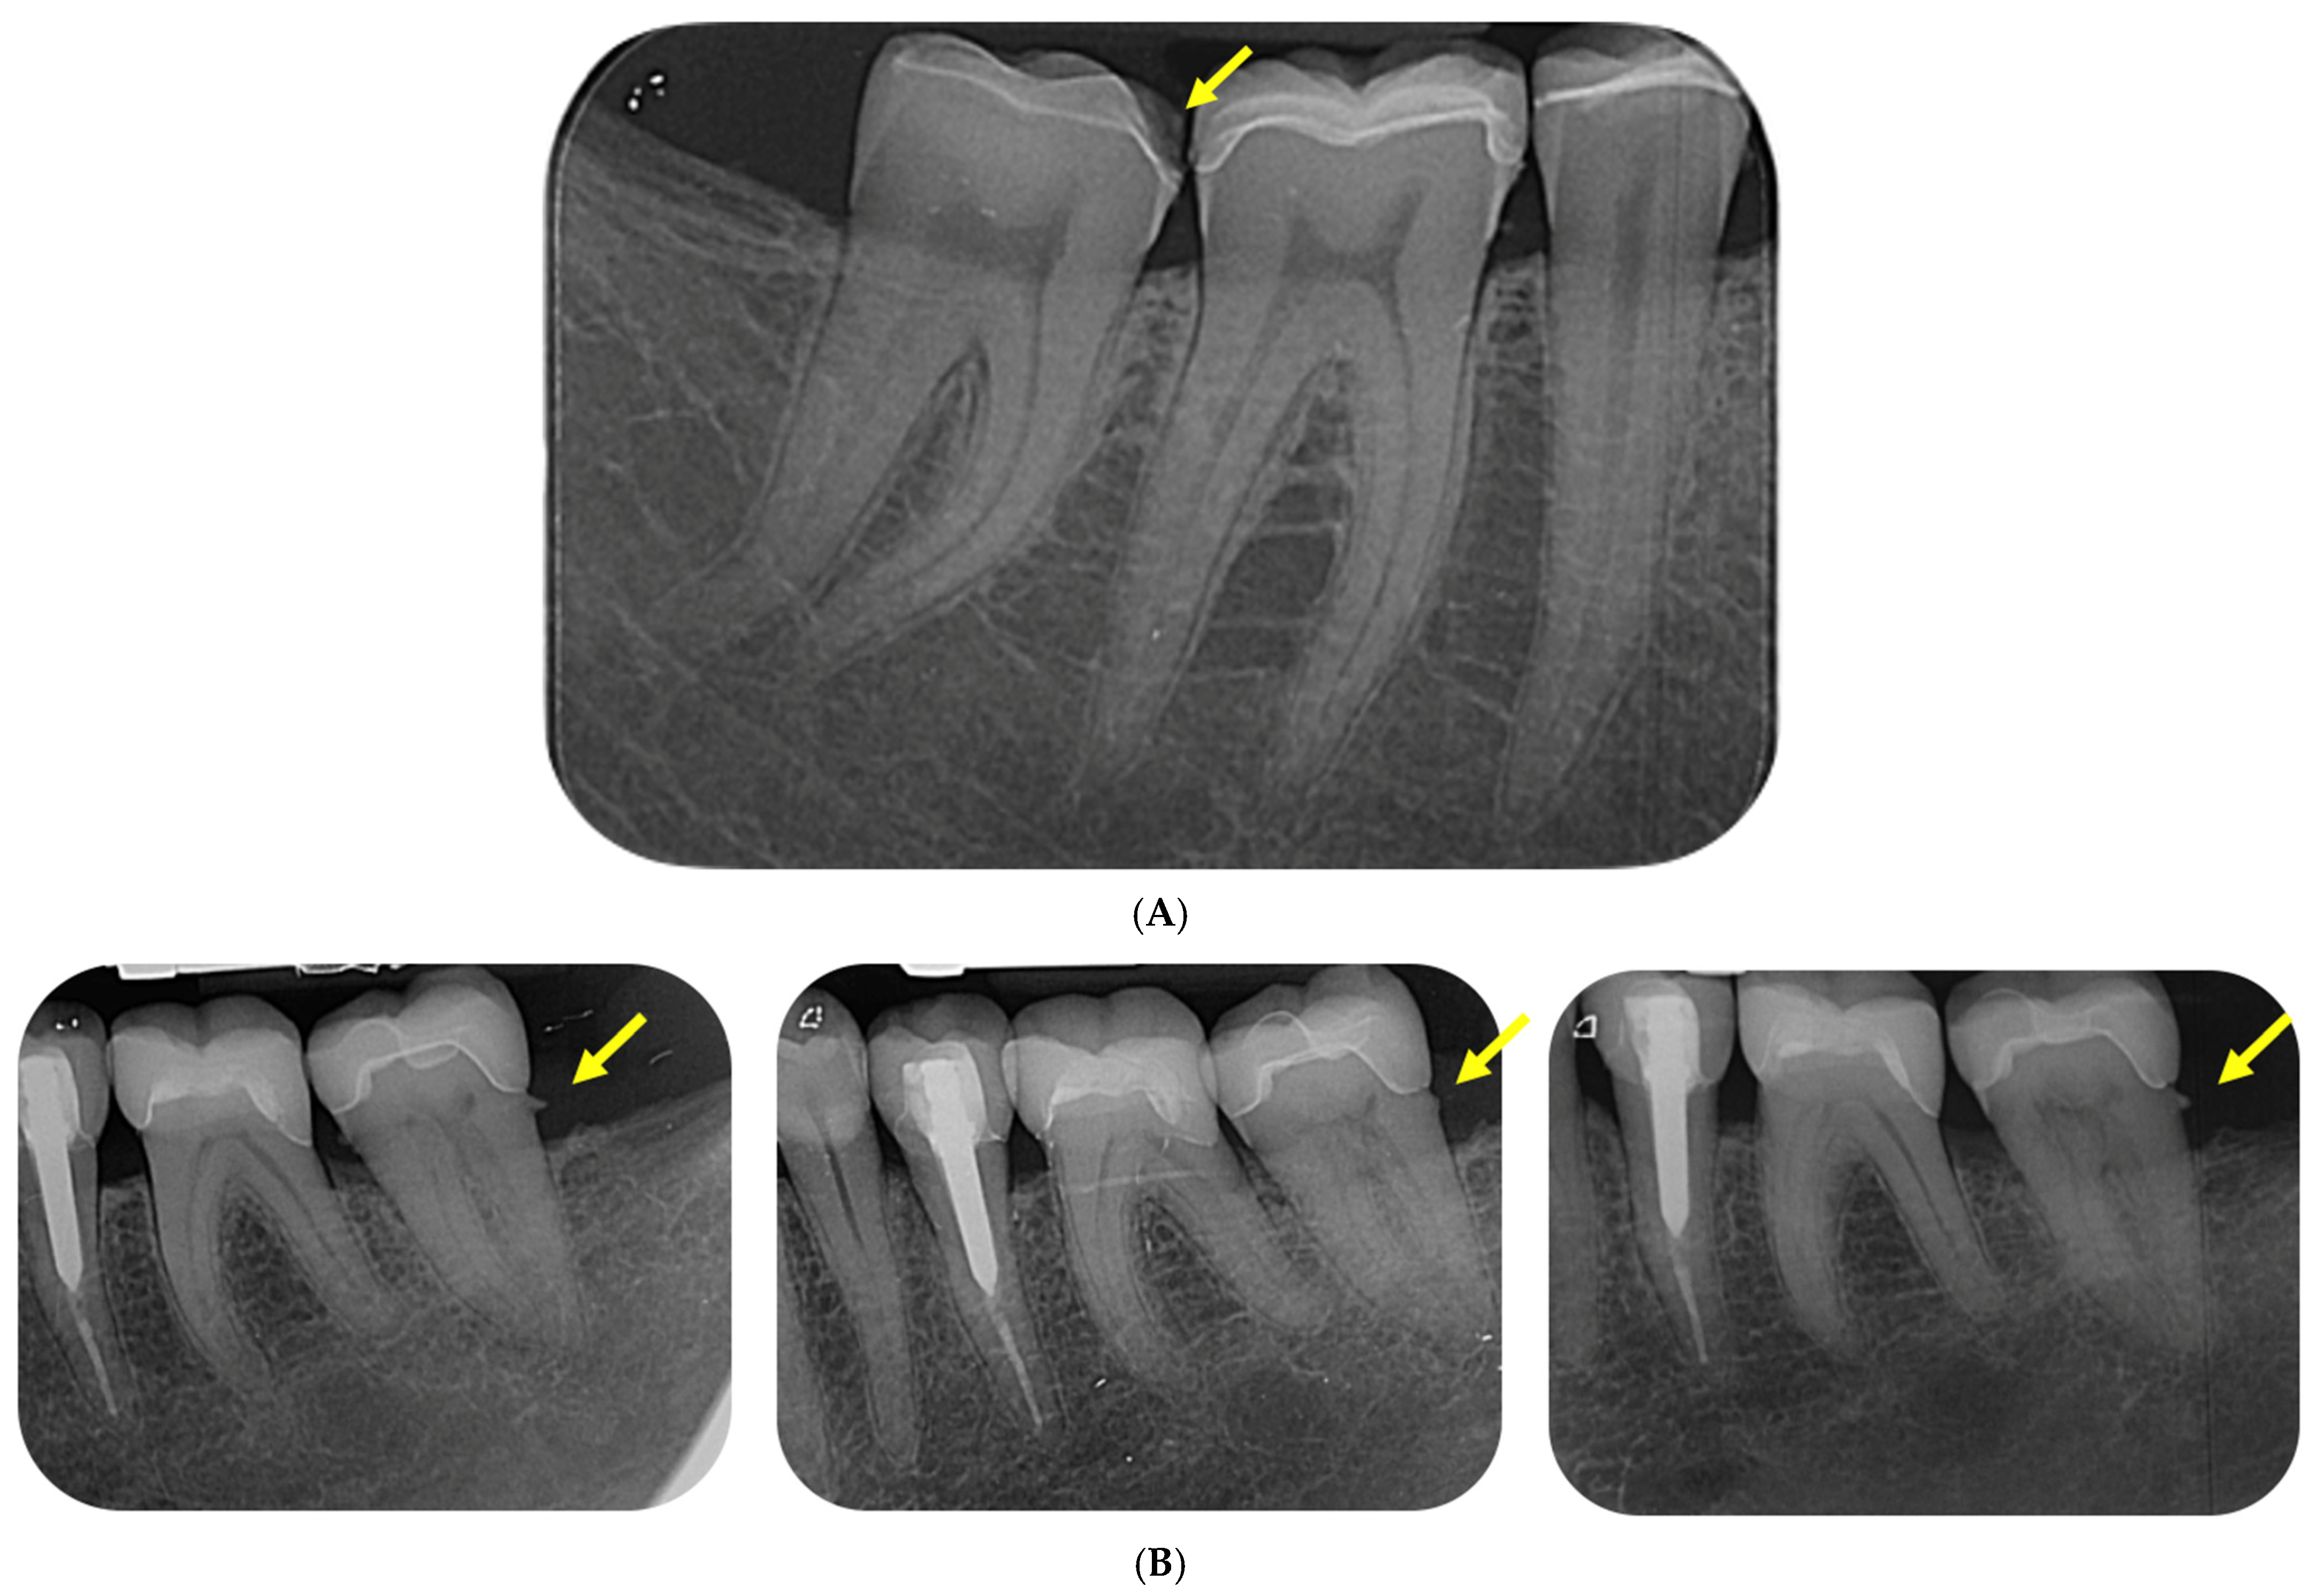

Figure 4.

(A). The radiograph shows cohesive fracture of medial side of lower-right second molar (#47); (B). The radiographs show postoperative monitoring status of #36 and 37—in second, fifth, and tenth year. There is a gap formation on the distal gingival base (yellow arrows) of tooth #37. In the monitoring of tooth #36, there are no radiographic signs of gap formation.

Back in 2000, Hayashi M. et al. evaluated the quality of feldspar ceramics after eight years in vivo. Durability was observed in 80% of feldspar ceramic inlay restorations after eight years (Kaplan–Meier method), although at six-year reporting, it was 92%, which differs from the results obtained in the present study—95.35% for both 5-year and 10-year follow-up. A change was observed from the 5-year period to the 10-year period, where the “Charlie” rate increased from 1.16% to 3.49%, or from one clinical case to three of the total number of followed cases (n = 86) (Table 2). The results show that the “Charlie” grade under criterion 6—“Marginal integrity”—fracture of the restoration or missing part or the entire obturation, leads to the replacement of the ceramic restoration with a new one three times in a 5-year period (from the 5th to the 10th year), but the increase in durability is related to the increase in the resistance of the materials and the increase in their strength (Figure 2 and Figure 3). Hayashi M. et al.’s follow-up revealed marginal fractures in 11 restorations (22%), with 5 (11%) experiencing volume fractures for the first time in the previous two years. We observed recurrent caries in 3 (7%) cases and marginal staining in 14 (31%). SEM evaluation revealed marginal microfractures in 77% of the restorations, wear in 36%, and edge wear in 74% at eight years. No significant difference was observed between molars and premolars [46]. One of the cases (#47) with cohesive fracture in the present clinical trial is presented in Figure 4A.

One of the serious problems that has remained for decades is still the impossibility of maximum adaptation in the marginal approximal areas where the level is below or at that of the interdental soft tissues. The clinical study included a tooth that we have been following for more than 10 years, with a radiographically diagnosed cleft at the distal gingival base. Due to the patient’s lack of symptoms, the case is being followed for longer, but the change in the indirect restoration is also planned (Figure 4B).